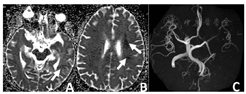

腰穿及影像学检查:腰穿见有清亮脑脊液流出,测压150 mm H2O;脑脊液体液细胞学:淋巴细胞93%、激活性淋巴细胞3%、激活性单核细胞2%、红细胞偶见,考虑存在穿刺伤;脑脊液分析(流式法):潘氏反应试验阳性(2+)、白细胞203×106/L(参考范围:0~8×106/L)、单个核细胞数198×106/L、单个核百分比97.6%;脑脊液生化:脑脊液总蛋白113.4 mg/dl(参考范围:0~50.0 mg/dl)、脑脊液糖94.7 mg/dl(参考范围:45.0~79.2 mg/dl)(指尖血糖14.0 mmol/L);血液、脑脊液细菌培养、宏基因测序阴性。双侧锁骨下动脉彩超:右侧锁骨下动脉斑块形成(狭窄率<50%),左侧未见明显异常;颈动脉彩超:双侧颈动脉球部斑块形成(狭窄率<50%),双侧颈总、颈内、颈外动脉、椎动脉未见明显异常;下肢深静脉彩超未见明显异常。胸部CT:右肺及左肺上叶尖后段散在微小结节。2019-08-08颅脑CT血管造影(CTA):左侧颈内动脉颈段末段及岩段节段性狭窄,相应管腔中-重度狭窄,远端分支较对侧稍显稀疏;双侧颈内动脉虹吸部多发钙化斑块,未见狭窄;右侧椎动脉颅内段钙化斑块,轻度狭窄;左侧大脑后动脉P1段局限性狭窄(图2)。颅脑MRI增强:左侧额顶枕叶脑沟内多发异常信号,左侧海绵窦较对侧增宽,左侧颈内动脉周围环形低信号(图3),建议进一步检查。2019-08-20颅内动脉斑块高分辨磁共振成像(HR MRI):考虑蝶窦炎致左侧海绵窦血栓性静脉炎,伴左侧颈内动脉(left internal carotid artery,LICA)大部腔内血栓形成,左侧大脑半球多发亚急性梗死;RV4近段易损斑块,管腔轻度狭窄(图4,图5,图6)。

注:A~D箭头所示为左侧额顶枕叶脑沟内多发异常信号;E、G、H箭头所示为左侧海绵窦较对侧增宽,F箭头所示为左侧颈内动脉周围环形低信号;MRI=核磁共振成像

注:箭头所示为左侧基底节区、左额叶白质及左额顶叶皮层区见多发散在点片状DWI高信号影;DWI=核磁弥散加权成像

头痛是本例患者最初的临床症状,导致CST的误诊较为常见,因此影像学检查对于该罕见疾病的确诊至关重要。SCHUKNECHT等[12]研究表明,切片厚度为3 mm以下的颅脑CT可以显著提高诊断CST的能力。CST直接体征包括海绵窦扩张或填充缺损,有几项研究发现侧壁隆起也是CST最常见和最敏感的影像表现[13]。CST的间接影像学包括颈内动脉海绵窦段变窄或闭塞、海绵窦壁相邻硬脑膜强化增强、眼球突出或继发性血栓形成—特别是上眼静脉、岩静脉或乙状窦[14,15]。本例患者在颅脑MRI增强可见左侧海绵窦区增宽、扩张(图3),颅脑CTA提示颈内动脉狭窄,经过HR MRI证实为血栓(图6)。有文献报道全脑血管造影也为诊断CST的有效方法,然而只有42%的患者能够看到海绵窦,因此全脑血管造影不被作为常规检查或早期检查[16,17]。

本例患者临床症状最初只有头痛,后逐渐出现上睑下垂及眼肌麻痹,但全程无明显的眼球突出、结膜水肿,是导致患者延误诊断的主要因素。CST相关的血栓性静脉炎还可能会扩散到颈内静脉,出现Lemierre综合征[21]。同时感染可以通过颈静脉扩散到肺血管系统,导致肺脓肿、肺炎或脓胸[22]。CST最危险的并发症是海绵窦感染通过无瓣膜硬脑膜窦或脑静脉和导静脉传播,出现硬膜下脓肿、脑脓肿和颅内静脉窦血栓形成等颅内病变[23]。CST的脑膜旁炎症或明显的细菌从海绵窦迁移到脑脊液中可能分别导致脑炎或脑膜炎。此外,感染可引起血管炎,导致走行于海绵窦的颈内动脉痉挛[24]、血栓形成致狭窄或闭塞[18]。多达30%的CST幸存患者会出现长期后遗症,包括动眼神经麻痹、失明和垂体功能不全[25]。如本例患者颅脑MRI增强可见左侧额顶枕叶脑沟内多发异常信号,结合患者DWI考虑脑梗死引起的血-脑脊液屏障破坏后出现强化,不考虑颅内转移病变(图3)。本例患者颅脑CTA证实其存在明显LICA重度狭窄(图2D),本例患者梗死部位均在颈内动脉供血区(图4,图5),12 d后行颅脑HR MRI证实颈内动脉闭塞,考虑为血栓形成导致(图6)。海绵窦段颈动脉壁炎症目前被认为是缺血性并发症的来源,本例患者合并多发脑梗死,虽然存在脑血管病危险因素糖尿病,颈内动脉超声提示颈内动脉斑块形成,辅助检查颅脑CTA可见明显颈内动脉重度狭窄,但患者脑梗死面积非颈内动脉闭塞大面积梗死,而是多发散在梗死;颅脑HR MRI可见颈内动脉充填物为长条形的血栓信号影,未见动脉粥样硬化斑块信号影,与海绵窦段颈动脉壁炎症致颈内动脉血栓形成有关,因此考虑本例患者脑梗死机制可能为血栓栓塞机制。